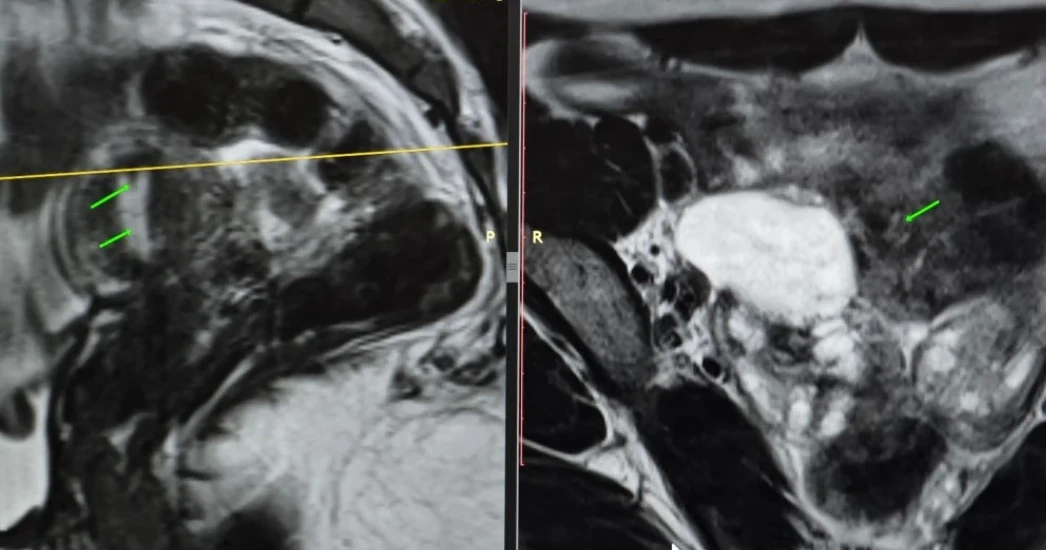

Классные тератомы. 30 лет.

В ОРАЦ есть интересный момент: когда речь о тератоме, то надо оценить, есть ли значительное количество ткани, накапливающей контраст. Субъективная вещь. Один сочтёт, что значительное, другой сочтёт, что не значительное. Но в первом случае это будет четвёртая категория и опухоли надо удалять, а во втором случае это будет вторая категория, и можно просто спокойно понаблюдать. Только что переубедил коллегу написать двойку вместо четвёрки по этим картинкам.

Кривую показываю на всякий случай, она на присвоение категории в данном случае не влияет, но дополнительно успокаивает, что ли. А зубчатость её объясняется тем, что исходные изображения и изображения после субтракции представляют собой одну серию, а вручную их разделять мне было лень. На информативность кривой это никак не влияет.

Видно, что в миометрии контраст накапливается гораздо быстрее и гораздо сильнее. То есть, если бы это на что-то влияло, то эту кривую надо было бы расценить, как кривую низкого риска.